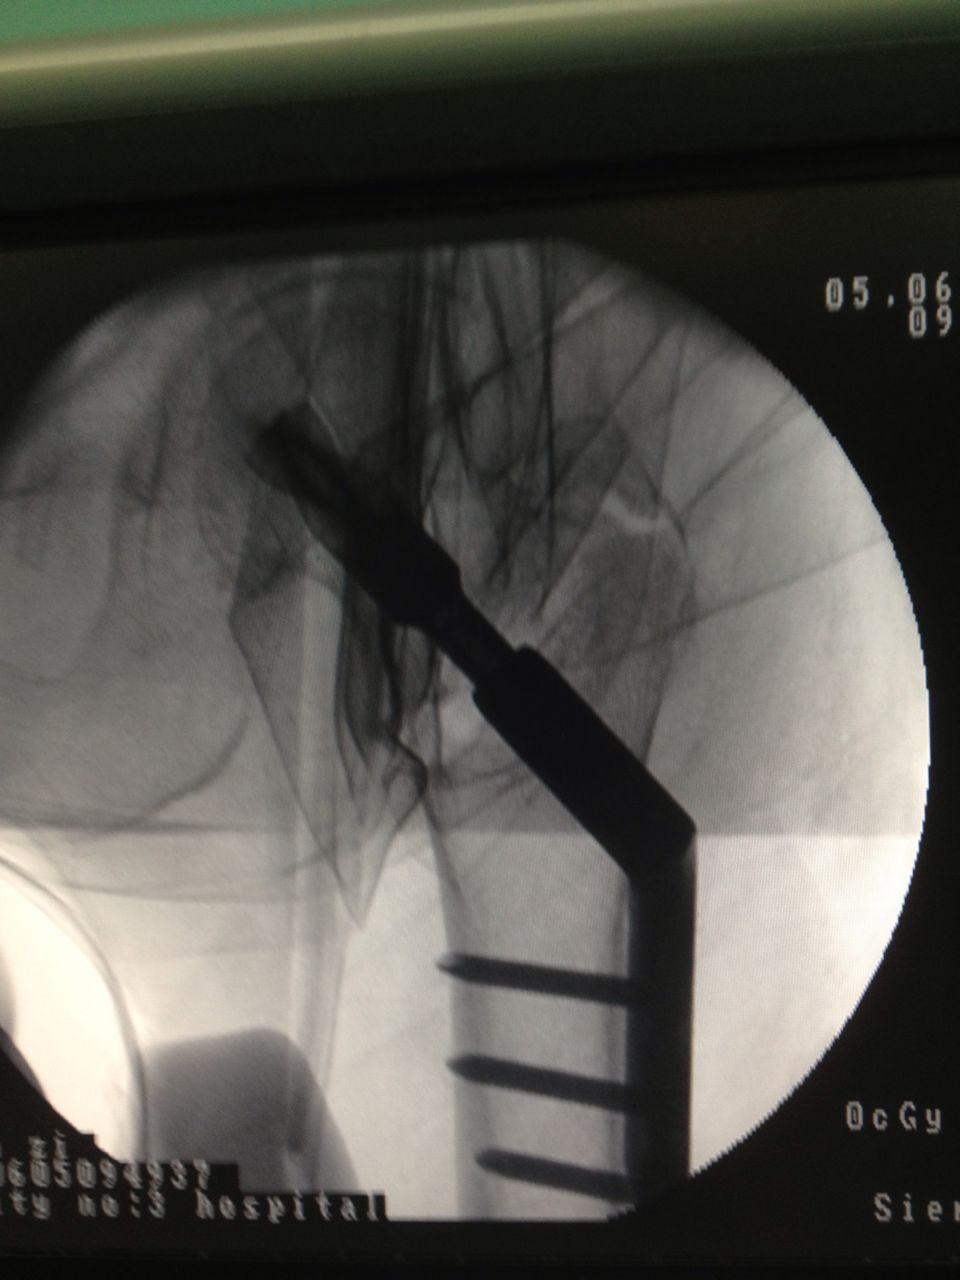

老人应选择何种治疗方案?第三医院骨科、心内科、麻醉科等多科专家组成的专家组认真仔细分析病情,决定采用髋关节微创植入内固定术。6月4日,老人接受手术,在手术牵引床上,通过C臂X光机透视,不切开骨折端闭合牵引复位,在老人骨折处复位到最佳状态时,刘忠国在骨折处开出5公分的口进行螺旋刀片动力髋固定,最大程度减少手术损伤,促进骨折端提早愈合。

手术很成功,老人术后6-8小时就能坐起,第二天已能下床略走几步。恢复行走的林老太竖起大拇指,直夸三院骨科医生技术高超。